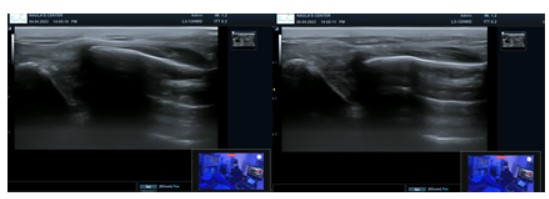

Al examen físico, rangos de movimiento del hombro derecho no valorables por el dolor.  Se realiza evaluación física eco-asistida, donde se evidencia el desplazamiento cefalo-caudal de la clavícula de manera dinámica (signo de la tecla piano EA (+)) (Figura 3); de la misma manera se realiza en sentido antero-posterior, donde se identifica la traslación en este eje (signo de la tecla de acordeón EA (+)) (Figura 4). Lo cual nos pone en manifiesto la presencia de una inestabilidad biplanar.

Figura 3. Signo ecográfico tecla de piano

Figura 4. Signo ecográfico tecla de acordeón.